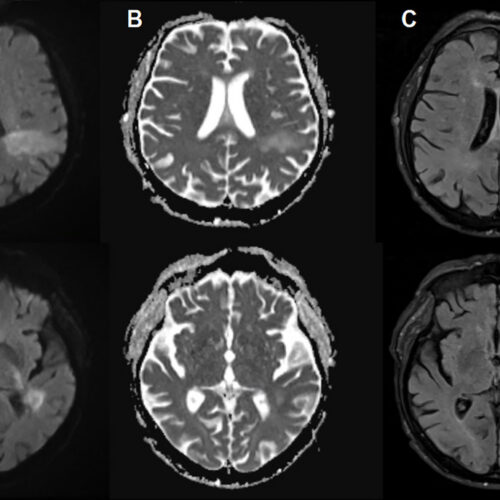

In PML, the new disease-causing virus or “PML-type” JC virus actively invades the brain, blowing up specific brain cells, including the cells that form the insulating myelin sheaths that protect nerve cells. This leads to extensive demyelination, which results in nerve cell dysfunction and death. On imaging, PML can show up as signature lesions in the brain. Those imaged lesions, paired with test findings of JC virus DNA in cerebrospinal fluid, are how PML is diagnosed. But for patients experiencing PML, the symptoms can mimic everything from a stroke to multiple sclerosis, causing problems speech impairments, visual defects, motor dysfunction, and seizures.

Initially, they thought his neurologic problems were due to uremic encephalopathy, decreased brain function from toxin accumulation during kidney failure. They treated him with dialysis, but his word-finding difficulty only worsened. At that point, they did brain imaging, which revealed lesions seen in PML cases. Soon, testing on his cerebrospinal fluid confirmed the presence of the JC virus in his central nervous system. Two days later, the patient died.